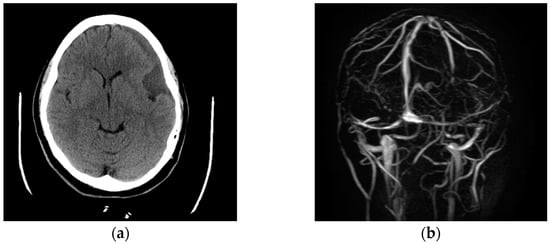

A 31-year-old female with no significant past medical history presented with 4 weeks of progressive bilateral vision loss, headache, and diplopia. She was initially diagnosed with migraines, but her symptoms persisted, prompting a visit to the Emergency Department. On physical examination, the patient’s right eye had a lateral gaze palsy and perceived motion only, whereas her left pupil was nonreactive with impaired color and light perception in that eye. No other neurological deficits were appreciated. Imaging studies demonstrated a left anterior temporal pole arachnoid cyst with a 19 mm left subdural hygroma with mass effect causing 4 mm of left to right midline shift, most concerning for a ruptured arachnoid cyst (Figure A1a).

The patient was taken to the operating room for a left frontal burr hole for drainage of her subdural hygroma. Post-operatively, she continued to have headache and minimal improvement in light perception bilaterally. Lumbar puncture demonstrated elevated intracranial pressure (ICP) with an opening pressure of 30.4 cmH2O consistent with idiopathic intracranial hypertension; magnetic resonance (MR) brain and MR venogram showed left transverse sinus stenosis (Figure A1b). Subsequently, a right frontal external drain (EVD) was placed for ICP management, after which there was significant improvement in the patient’s vision.

Figure A1. (a) (left) Axial CT (head showing left-sided subdural collection and mass effect on the adjacent cerebral cortex. (b) (right) MRA brain demonstrating the stenotic transverse sinus.